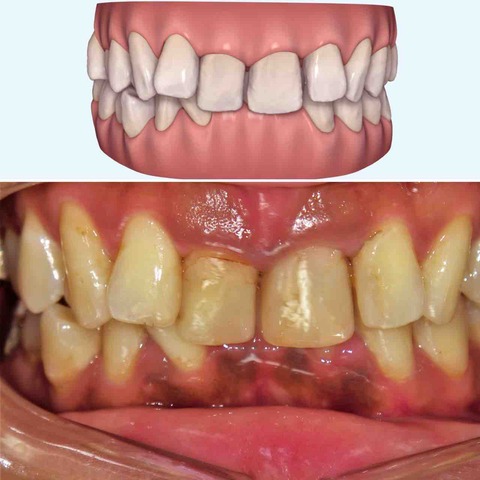

上の歯の比較

下の歯の比較

噛み合わせの比較。

患者さんは平成23年生まれの13歳とあごの成長が残っている世代だった為、あごの成長をコントロールすることもできわずか10か月で終了することができた。